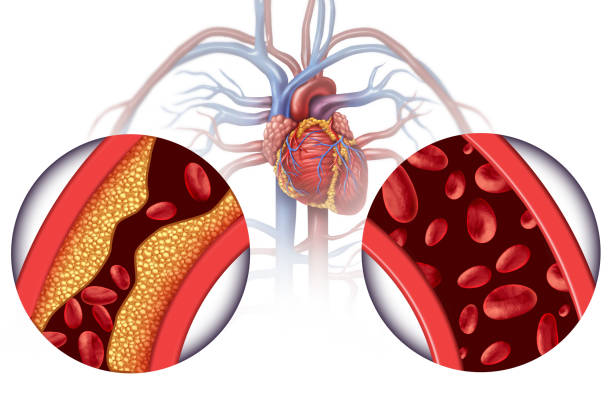

Een goede doorbloeding is cruciaal voor het lichaam om voedingsstoffen en zuurstof efficiënt te kunnen transporteren en goed te laten functioneren. Helaas kunnen er soms blokkades ontstaan in de bloedcirculatie, waardoor belangrijke lichaamsdelen een tekort aan zuurstof kunnen krijgen. Het is daarom van groot belang om snel in te grijpen bij dergelijke situaties, zodat de balans hersteld kan worden en het lichaam optimaal blijft functioneren en zich goed blijft voelen.

Wanneer een deel van het lichaam minder doorbloed is als gevolg van een blessure of medische aandoening, kan dit leiden tot verstoringen in de zenuwsignalen die tijdelijk worden verstoord en anders worden doorgegeven. Deze versto- ringen kunnen resulteren in een verminderde responsiviteit van de spieren in dat specifieke gebied, waardoor de functionaliteit van het lichaamsdeel kan afnemen. Dit kan op zijn beurt leiden tot een teruggang van kracht, coördinatie en flexibiliteit, waardoor de algemene gezondheid en mobiliteit van het individu kan worden aangetast.

Hoewel plotselinge veranderingen in de bloedcirculatie onverwachts kunnen voorkomen, zijn er maatregelen die genomen kunnen worden om de gezondheid op lange termijn te verbeteren. Het consumeren van voedsel met antioxidanten, regelmatig bewegen en voldoende ontspanning zijn hierbij van groot belang. Het regelmatig controleren van de bloeddruk en zorgen voor voldoende hydratatie spelen ook een essentiële rol bij het behouden van een gezonde bloedcirculatie.